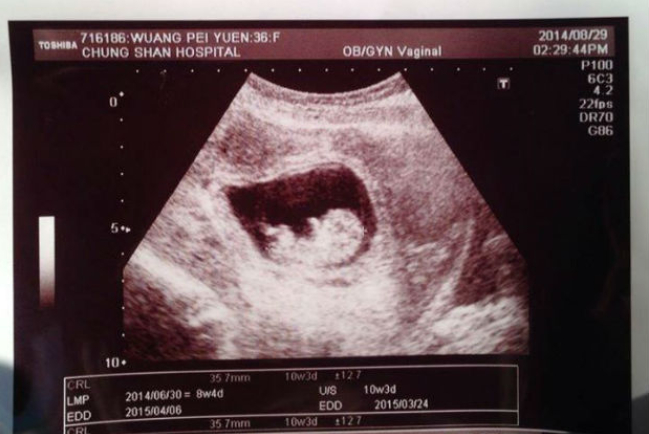

劉畊宏王婉霏懷第三胎 稱上帝所賜超乎所求